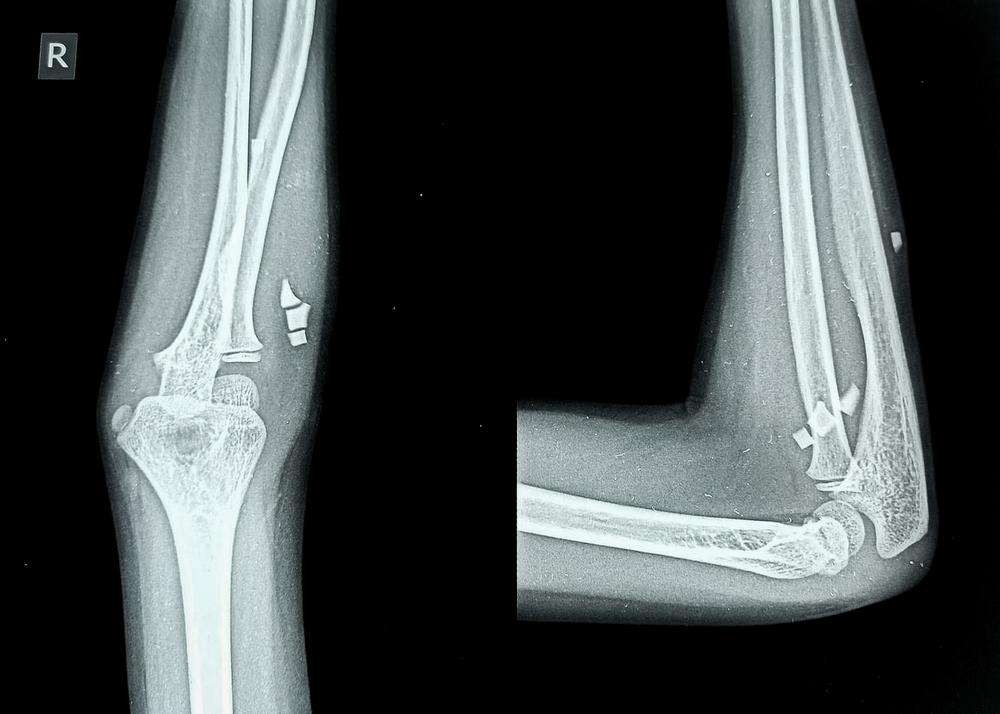

- Снимок в двух проекциях. Сначала прямой ракурс, затем боковой: предплечье сгибают под 90 , ладонь опускают вниз. Такая проекция раскрывает суставную щель, надмыщелки и венечный отросток.

- Тонкая просветляющая (радиопрозрачная) линия, проходящая через сустав. Линия свидетельствует о нарушении целостности костной ткани внутри сустава. Часто плохо визуализируется при стандартной проекции, поэтому рекомендуется дообследование с помощью КТ — это поможет точно оценить положение отломков и спланировать хирургическое вмешательство (например, остеосинтез).

- Неровный, «зазубренный» край локтевого отростка. Возможен мелкооскольчатый перелом. Наличие мелких отломков делает сращение сложным. Если кости неправильно срастутся, это может привести к ограничению подвижности и развитию посттравматического артроза. Необходим тщательный контроль восстановления.

- Спиралевидная линия перелома в диафизе локтевой кости. Возможен перелом Монтеджи. Серьезная травма часто сочетается с вывихом головки лучевой кости. Требует оперативного вмешательства — в противном случае возможна нестабильность сустава и нарушение функции предплечья.